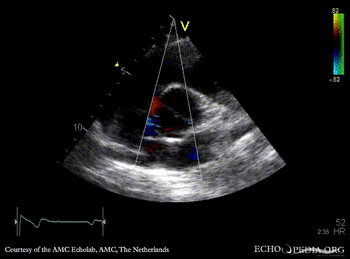

PLAX: dilated ascending aorta in patient with bicuspid aortic valve PSAX: bicuspid aortic valve

PSAX: Color Doppler, mild excentric aortic regurgitation Continuous-wave signal of transaortic flow: aortic bicuspid valve stenosis